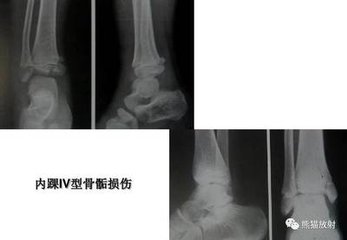

小时候骨骺损伤造成踝关节畸形

骨骺和骺板都是未成熟骨骼的生长位,也就是长个子的部位。骨骺损伤是涉及骺、骺生长板、骺生长板周围环(Ranvier区)、与生长相关的关节软骨及干骺端损伤。小儿骨折中大约15%涉及到骨骺损伤,骨骺的损伤多是在儿童青少年时期,活动度大损伤多。骺板的强度比肌腱、韧带的强度差,所以儿童关节部位的损伤,首先考虑到骨骺部位损伤的可能性。

骺板损伤除有一般骨折的并发症外,更重要的特有的并发症是可导致骨骼生长功能障碍。若一侧骨骺受到损伤,两侧生长不均衡,会造成肢体外翻或内翻等畸形或肢体不等长。对工作学习带来不便。其预后与受伤年龄、该骺板生长潜力和累及范围有关,发病年龄小、生长潜力大的骨骺受损,一旦发生并发症致畸程度严重。因此一定要对骨骺损伤引起足够重视。